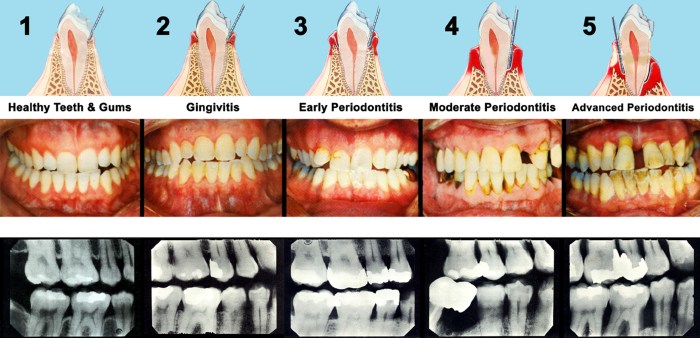

Understanding Gum Disease

Gum disease, also known as periodontal disease, is a common oral health condition that affects the tissues surrounding the teeth. It is primarily caused by the buildup of plaque, a sticky film of bacteria that forms on the teeth.